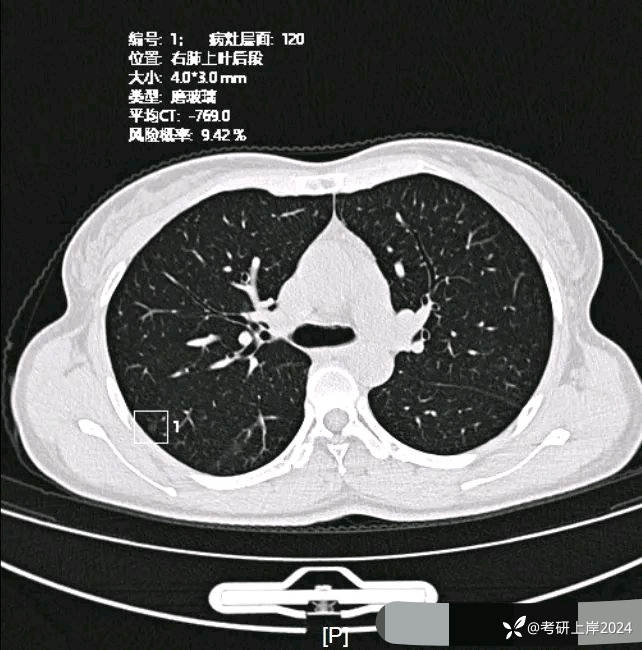

患者最近的检查有AI辅助诊断意见,找出的病灶分别如下:

病灶5:右上叶微小磨玻璃结节,轮廓较清,考虑肺泡上皮增生可能性较大;

病灶6:左上叶微小磨玻璃结节,轮廓较清,考虑肺泡上皮增生可能性较大;

病灶8:右上叶微小磨玻璃结节,轮廓较清,考虑肺泡上皮增生可能性较大;

病灶14:右上叶很淡密度微小磨玻璃结节,轮廓较清,考虑肺泡上皮增生可能性较大;